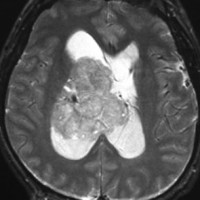

20代の男性の神経細胞腫です。側脳室の中のとても大きな腫瘍です。上段はガドリニウムという造影剤を入れた時のMRIです。下段の中央はCTですが,石灰化が見られます。脳外科の先生には,この脳室内腫瘍は一見transcallosal approach(経脳梁到達法)という手術で取れるように見えるかもしれませんが,そうではなくて,脳室の壁とくに上壁と側壁にくっついているのでなかなか取れません。この患者さんの場合は右の頭頂葉というところからtranscortical approach(経皮質到達法)で全摘出しました。後遺症もなく再発もなく術後10年が過ぎています。全部とれれば治ってしまう腫瘍です。